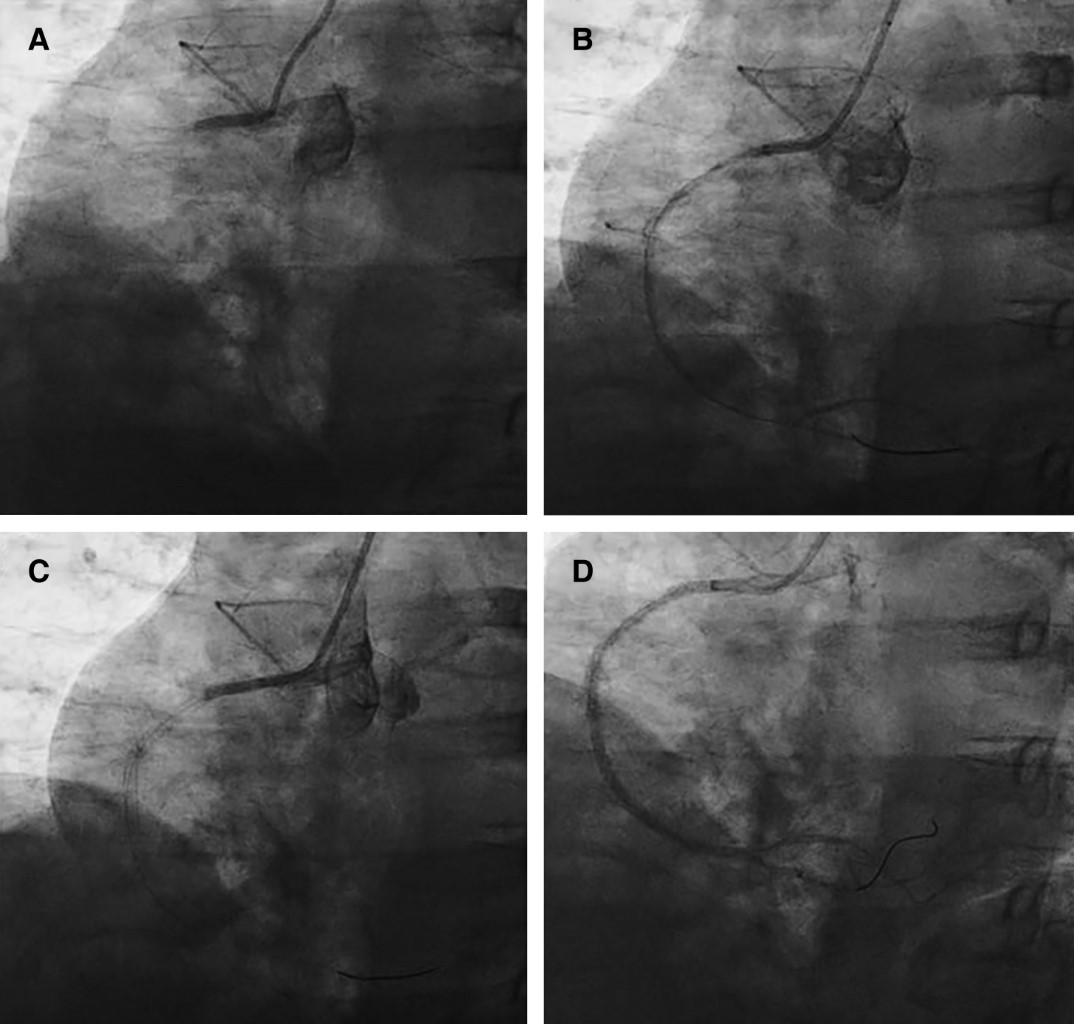

Se realiza coronariografía urgente, la cual evidencia oclusión trombótica total en la arteria coronaria derecha (ACD). Se practica angioplastia e implante de tres stents; después del procedimiento cursa con fenómeno de no reflujo y alta carga de trombo (Figura 4); se procedió a realizar tromboaspiración con un flujo final TIMI 2.

Se realizan lavados de adenosina intracoronaria e infusión de tirofibán y vasopresores en la Unidad de Cuidados Intensivos Cardiovasculares (UCIC). Durante su estancia, se realizó ecocardiograma transtorácico (ECOTT) donde se cuantificó una FEVI de 51%, índice cardiaco (IC) 1.3 L/min/m2, acinesia inferobasal, hipocinesia posterobasal y anteromedial, disfunción sistólica de ventrículo derecho y TAPSE 10 mm.